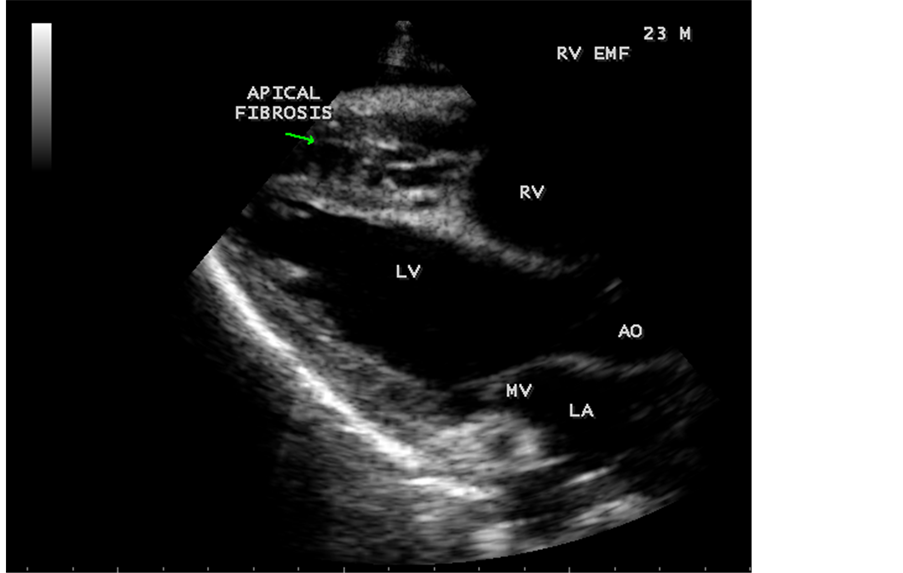

pressure 100/70 mmHg. Auscultation revealed diminished breath sounds on the right side of the chest with a dull note on percussion and a loud P2 (pulmonic component of second heart sound) with grade 2/6 soft systolic murmur over the lower left sternal border which increases in intensity with deep inspiration (Carvallo’s sign) suggesting tricuspid regurgitation. ECG revealed no arrhythmias and X-ray chest showed right- sided pleural effusion and extensive calcification over the cardiac shadow as shown in Figure 9. Transthoracic echocardiography revealed apical fibrosis of right ventricle, moderate pericardial effusion, right atrial dilatation as shown in Figure 10 and Figure 12, suggesting right ventricular endomyocardial fibrosis and severe tricuspid regurgitation as in Figure 11, Figure 13 and Figure 14 indicates coexisting pulmonary hypertension due to pulmonary damage caused by tuberculosis as shown in Figure 13 and free RV outflow tract as in Figure 15. Patient was treated with antituberculous drugs, antifailure measures such as digoxin and diuretics, ascites fluid tapping and antibiotics. He showed mild improvement in his symptoms.

Figure 10. Parasternal long axis view showing RV (right ventricular) apical fibrosis suggesting EMF (endomyocardial fibrosis) in a 23-year-old male with tuberculosis.